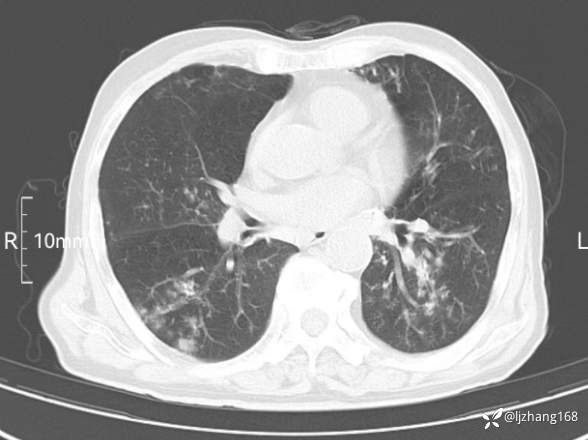

老年男患,咳嗽,气短,双肺多发间质性病变,何种感染?(有结果)

辅助检查:胸部CT:双肺肺气肿,间质性病变,血气分析:PH 7.413, PCO2 29.2mmHg, PO2,81.8mmHg,乳酸 3.3mmol/1,剩余碱-4.0mmol/1,HC03 18.8mmol/1。全血超敏C反应蛋白:超敏C反应蛋白 135.60 mg/L、 白细胞 14x19^9/L,中性粒细胞11.6x10^9/L。